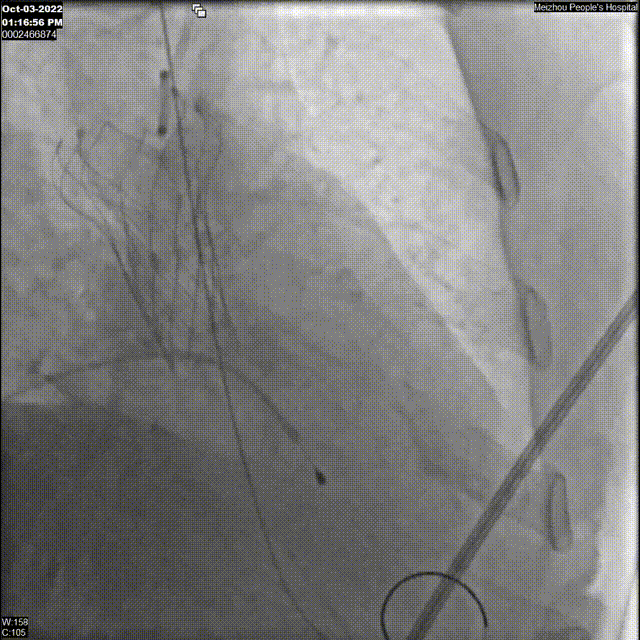

手术过程

3、主动脉根部影像

主动脉根部造影

18F球囊预扩张影像

瓣膜植入影像

18F球囊后扩影像

瓣膜最终植入结果